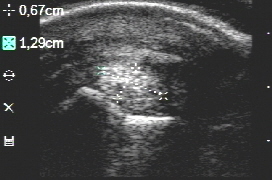

Zerrungen des Seitenbandes des Hufgelenkes lassen sich mittels Ultraschall oft gut nachweisen. Die größte Aufklärungsquote erbringt MRT. In den meisten Fällen findet man neben einem Kollateralbandschaden auch weitere Veränderungen im distalen Gliedmaßenbereich wie die Erkrankung des Hufgelenkes und des Strahlbeinkomplexes.

- Linkes Bild normales Seitenband, rechtes Bild geschädigtes Seitenband des Hufgelenkes

- Beispiel für Faserrisse im Kern des Seitenbandes (hypoechogene - markierte schwarze Zone im Zentrum des Bandes)